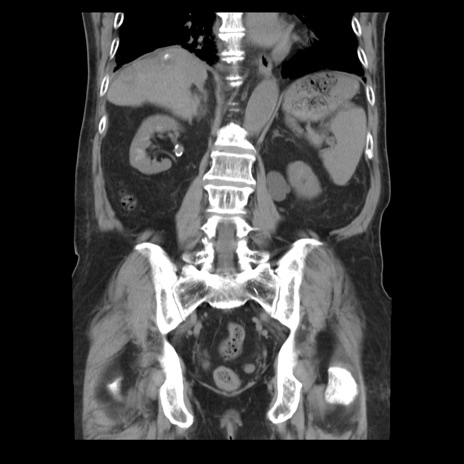

症例21(冠状断像)

【症例】70歳代男性

【主訴】腹痛

【現病歴】肝硬変・肝細胞癌にてかかりつけの方。約9時間前に食後より腹痛出現。症状が徐々に増悪し、嘔吐出現したため来院。

【既往歴】肝硬変、肝細胞癌(RFA、TACE後)

【身体所見】意識清明、表情苦悶様、BT 36℃、BP 129/78mmHg、P 88bpm、SpO2 97%(RA)、右上腹部から心窩部にかけて圧痛あり、反跳痛なし、筋性防御あり。

【データ】WBC 5800、CRP 0.16